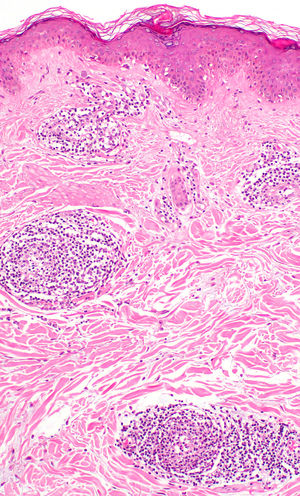

El estudio histopatológico de una biopsia del borde de una placa de la cara posterior del muslo izquierdo, evidenció una mínima espongiosis epidérmica con una paraqueratosis focal. En la dermis superficial se observó un infiltrado inflamatorio discreto perivascular «en manguito», de predominio linfohistiocitario y sin afectación de las paredes vasculares (fig. 2). La tinción de PAS no mostró la presencia de elementos fúngicos. La inmunofluorescencia directa fue negativa.